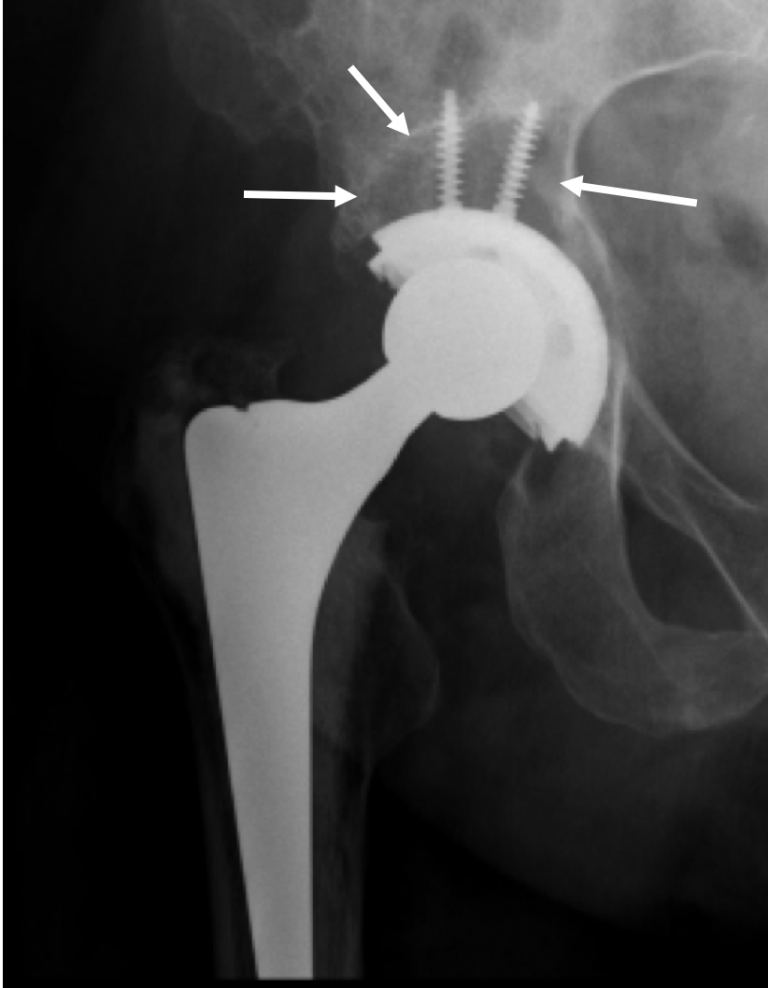

From www.wjgnet.com

Screw of the iliopsoas muscle causing lateonset pain after Hip Replacement Post Op Bleeding studies have shown a reduction in blood loss after the use of a posterior approach in total hip replacement. [ 5, 6, 7] others have. the international hip society partnered with sicot pioneer to present its webinar on strategies to prevent early. although there is a high risk of bleeding after total hip arthroplasty (tha) and total. Hip Replacement Post Op Bleeding.